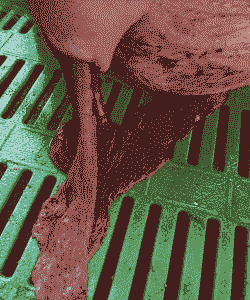

产道出血

原因:助产时损伤产道、老龄母猪子宫脆弱或仔猪胎位性问题可能导致产道内膜损伤,引起出血。

症状:阴户完整无损,出血呈水珠状。

产道出血的救治

止血:先静脉推射止血敏(酚磺乙胺)10mL,然后结扎外阴动脉血管。具体操作包括准备缝合针线、消毒水,寻找出血点并进行结扎,直到完全止血为止。

固定好母猪,使用产道打开器扩充产道,寻找出血点,用浸润过肾上腺素的纱布条压迫出血点,直至不出血。如果血流不止,半小时后还需补打止血敏。